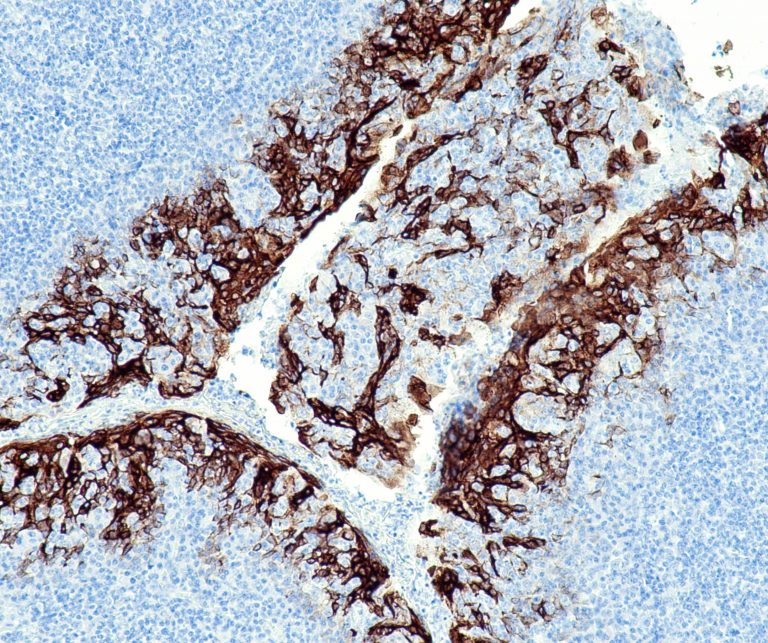

Vascular Pathology